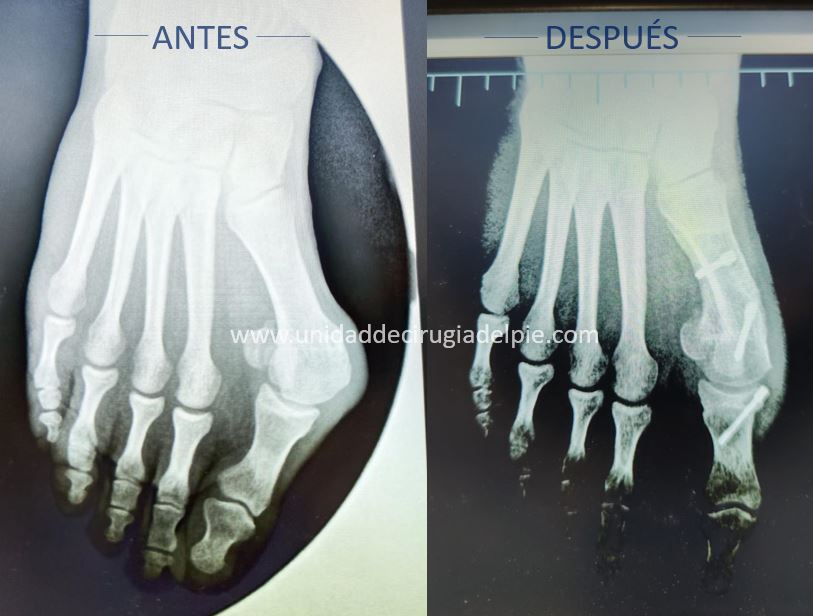

Este mes os traemos el caso de un hombre de 30 años que fue intervenido quirúrgicamente en nuestra clínica por una patología de juanete (hallux valgus) en el pie derecho. Se le realizó una cirugía convencional, mediante la cual se llevó a cabo la corrección de la dolencia a través de la realineación del primer dedo del pie, logrando así una notable mejoría del dolor.

El paciente realizó una recuperación de aproximadamente un mes, durante la cual se le realizaron curas semanales y se reforzó la mejoría manteniendo el pie en alto y utilizando un calzado postoperatorio específico de manera reiterada.